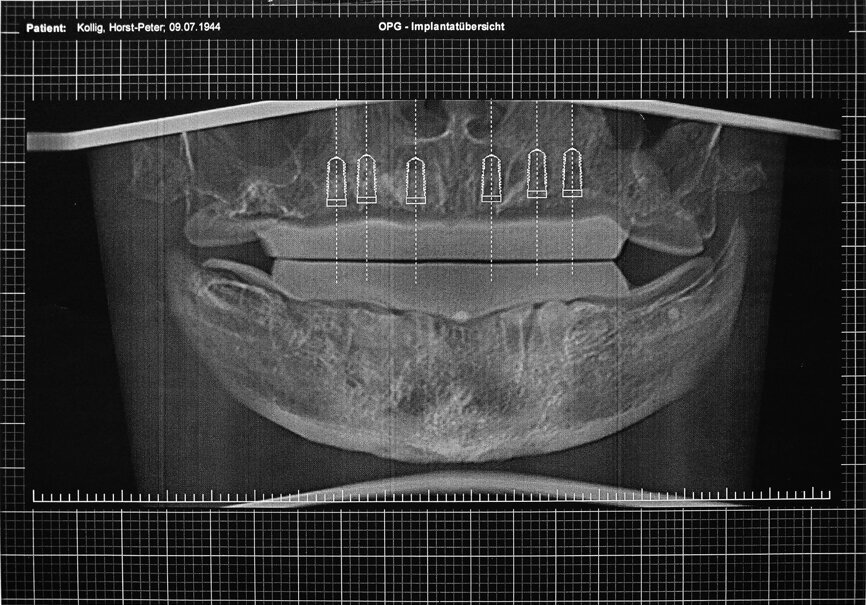

Figs. 12a et b : Tomographie panoramique dentaire virtuelle montrant les positions des implants numériquement définies en 3D dans le maxillaire (a) et la mandibule (b).

La radiographie panoramique dentaire a révélé une perte osseuse d’environ dix pour cent dans la dimension verticale et de quinze pour cent dans la dimension horizontale dans le maxillaire et la mandibule. Après le diagnostic définitif et la planification, nous avons examiné les options de restauration possibles et les autres solutions. La mâchoire ayant été exposée aux rayons, une prothèse totalement a appui muqueux n’était pas indiquée, et la présence de la xérostomie ne garantissait pas une maintenance convenable d’une telle prothèse. Par conséquent, la seule solution médicale raisonnable et pratique était la pose d’implants dentaires, six dans le maxillaire et six dans la mandibule, suivie de la mise en place d’une prothèse fixe implanto-portée.

Le patient a été préparé pour le traitement implantaire guide par ordinateur. Une imagerie CBCT du patient portant le guide radiologique a été réalisée et les images DICOM acquises ont été traitées à l’aide du logiciel CTV. La planification effectuée avec ce logiciel a produit un rapport dans lequel les coordonnées de chacun des trois points médians des billes étaient définies et le prothésiste a donc pu orienter et reproduire le guide chirurgical (Figs. 12a et b). Les gabarits de forage ont été élaborés sur une réplique du maître-modèle à l’aide d’une technique de thermoformage. Par la suite, les manchons de forage ainsi que leurs douilles ont été incorporés dans le gabarit de forage constitue du modèle en plastique fabrique au moyen du procédé additif. La base transparente du gabarit a permis une évaluation peropératoire de la position de ce gabarit sur le tégument grâce à l’ischémie uniforme causée par la pression de contact pendant l’implantation (Fig. 13).